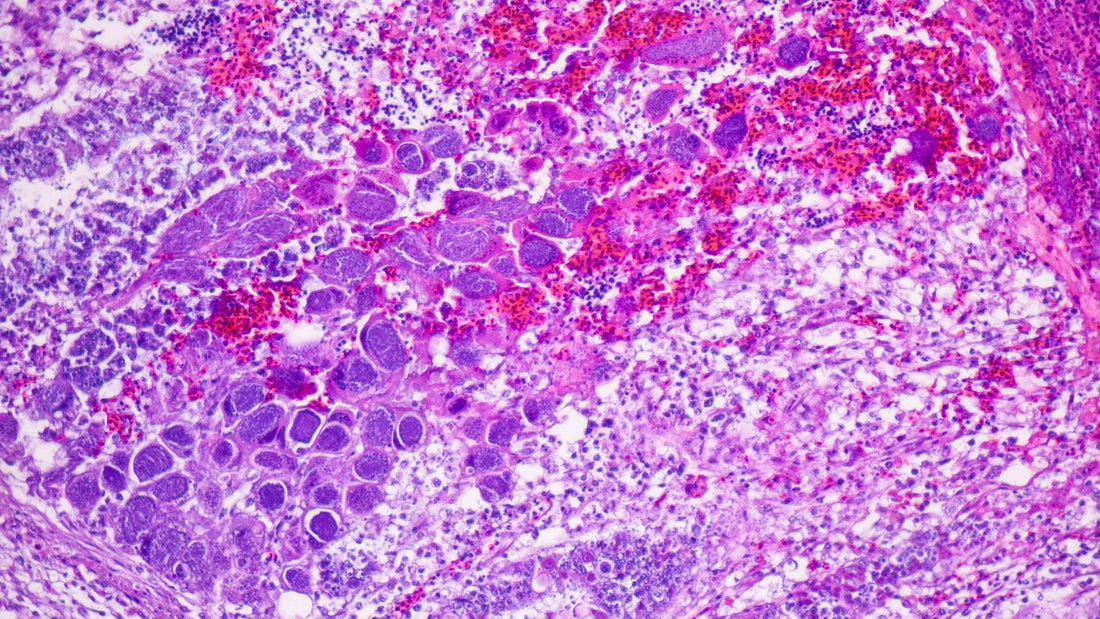

Coccidia are microscopic parasites that live in a dog’s intestines. They’re so small you can’t see them without a microscope, but their impact can be significant. These parasites are common in dogs, and while healthy adults might not show any signs, puppies and dogs with weaker immune systems are more likely to get poorly.

The most common type of Coccidia that affects dogs comes from a group called Isospora. Once inside your dog’s intestines, these parasites can multiply and cause a condition called Coccidiosis, which can lead to stomach upset and other issues.

Coccidia is usually diagnosed by looking at your dog’s poop under a microscope to spot the oocysts. Since Coccidia don’t always shed evenly, you might need multiple samples to confirm the infection. These tests can be done at home with a Worm Count Test or via your vet who may run other tests to check why your dog may be poorly.